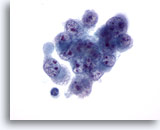

画像 5

肝FNA – 良性胆管細胞

良性胆管細胞の集塊。蜂巣状に配列し、均一な小型の核がみられます。

20倍

画像 5

肝FNA – 良性胆管細胞

良性胆管細胞の集塊。蜂巣状に配列し、均一な小型の核がみられます。

20倍